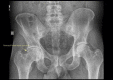

Case: A 27-year-old man with coxa profunda and a right acetabular labral tear presented for surgical re-evaluation after a postless arthroscopic labral repair was attempted at an outside institution and aborted because of inadequate distraction during portal placement. Arthroscopic labral repair with a perineal post was subsequently performed without complications.

Conclusion: Indications and limitations of postless hip distraction are seldom discussed in the literature. This report examines possible limitations of postless hip distraction for a patient with coxa profunda. Careful radiographic evaluation of hip anatomy may be essential for patients with deep hip sockets to determine the best-suited distraction technique.